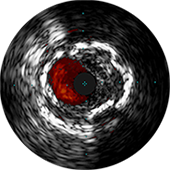

Изображение предоставил Аллен Джеремайас, врач. На изображении показано программное обеспечение SyncVision с функцией обнаружения устройств, которое позволяет легко визуализировать особенности проведения терапии.

Цифровой катетер для ВСУЗИ Eagle Eye Platinum

Система для визуализации и ко-регистрации данных SyncVision

ВСУЗИ